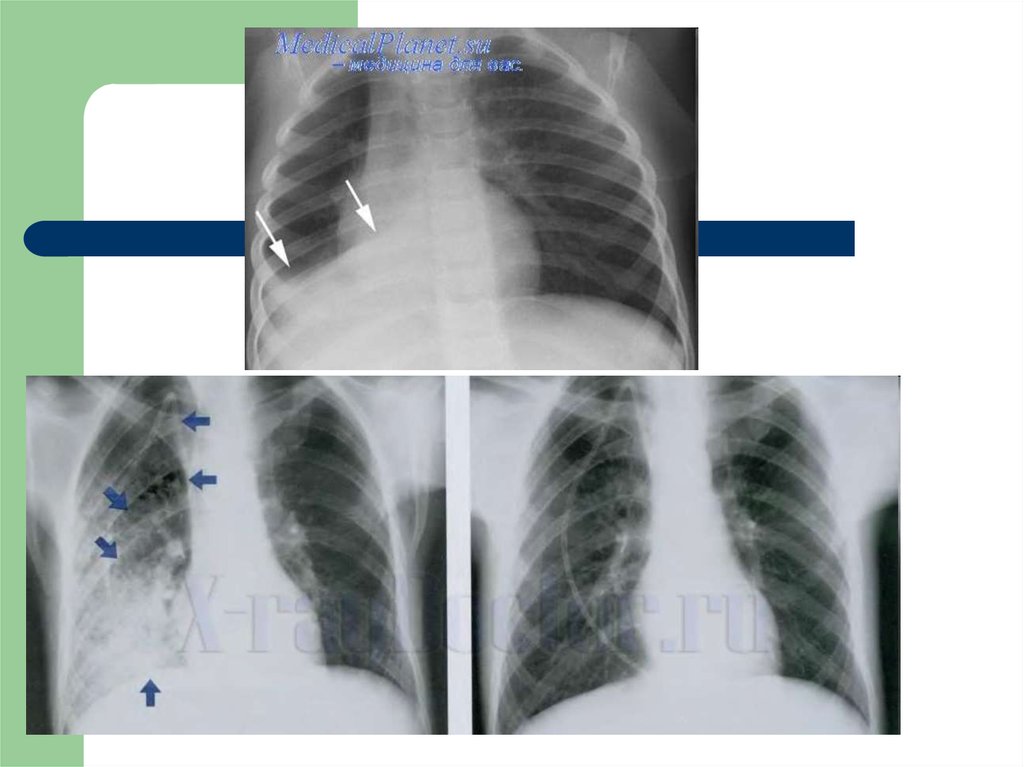

6. 3. Нарушение диффузии кислорода через аэрогематический барьер

Причины: Утолщение

и/или уплотнение

компонентов

альвеолокапиллярной

мембраны

7. 4. Нарушение диссоциации вентиляционно-перфузионного соотношения